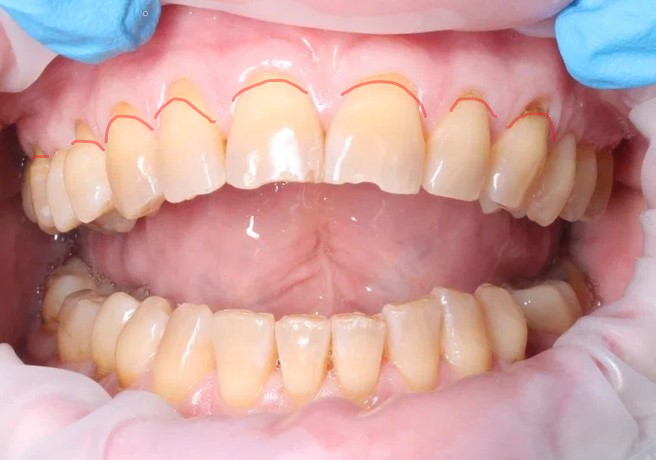

Простой пример - рецессии вследствие хронического генерализованного пародонтита. Причина - бактериальная биопленка (поддесневые зубные отложения) и реакция организма в виде воспаления, деструкции костной ткани.

Рецессии.

Зато чётко ведь видно, где эмаль а где корень?

А тут прямо таки можно увидеть линию раздела.

Если приглядеться, можно увидеть линию, разделяющую две зоны. Эмаль - светлее, более гладкая и лучше блестит.